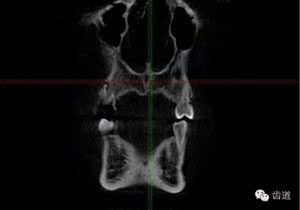

好的開(kāi)始就是成功的一半。通過(guò)CBCT了解根管的位置,形態(tài),方向。

檢查顯示:近頰及腭根充填恰填,遠(yuǎn)頰根管內(nèi)有少許充填物影像。根尖明顯低密度影像。